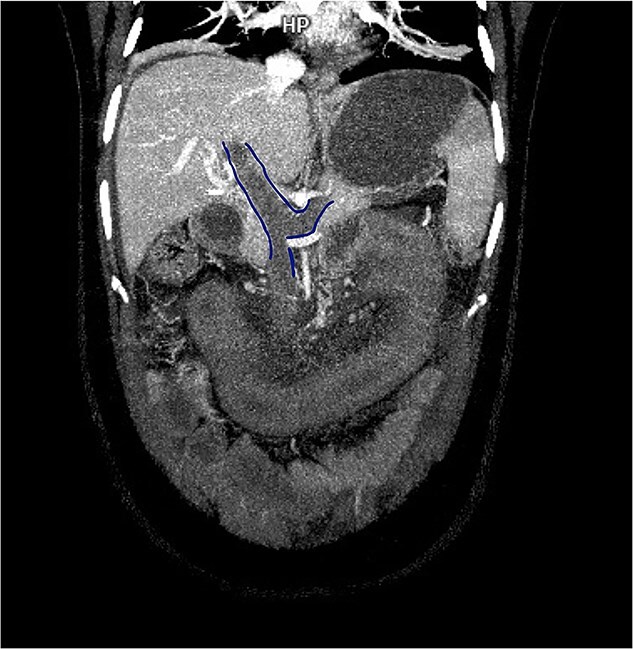

急性肠系膜静脉血栓形成是一种罕见且可能致命的肠道缺血原因。我们报告一个38岁的妇女异常子宫出血,与贫血,并长期使用醋酸甲孕酮。她表现出严重的腹痛、腹膜体征和全身炎症反应。计算机断层扫描显示门静脉、脾静脉和肠系膜上静脉血栓形成,空肠壁增厚。最初剖腹手术显示肠存活;开始全面抗凝。她后来出现穿孔,需要空肠切除术,随后再次手术治疗吻合口裂开。广泛的检查显示,除了使用黄体酮外,没有血栓前病变。本病例强调需要考虑激素制剂作为门-脾-肠系膜血栓形成的潜在触发因素,即使在没有合并症的年轻女性中也是如此,并需要寻求多学科、个性化的治疗,以平衡及时手术和保持肠道长度。

Acute mesenteric venous thrombosis is a rare and potentially lethal cause of intestinal ischemia. We report a 38-year-old woman with abnormal uterine bleeding, with anemia, and prolonged use of medroxyprogesterone acetate. She presented severe abdominal pain, peritoneal signs, and systemic inflammatory response. Computed tomography revealed thrombosis of the portal, splenic, and superior mesenteric veins with jejunal wall thickening. Initial laparotomy showed a viable bowel; full anticoagulation was started. She later developed perforation requiring jejunal resection and subsequent reoperation for anastomotic dehiscence. Extensive workup revealed no prothrombotic disorder other than progestin use. This case highlights the need to consider hormonal agents as potential triggers of porto-spleno-mesenteric thrombosis, even in young women without comorbidities, and to pursue multidisciplinary, individualized management to balance timely surgery with preservation of bowel length.